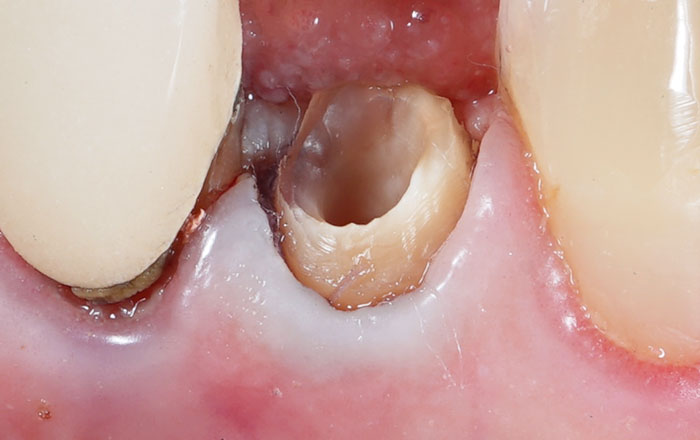

歯は大きく分けて、歯冠(しかん:歯茎より上の目に見える歯の部分)と、歯茎の下に隠れている歯根(歯の根っこの部分)で構成されています。

虫歯で歯冠がボロボロになっていても、歯根の状態が良ければ、それを土台として歯を復活させられる可能性があります。具体的には、以下の条件が揃っているかどうかがポイントです。

- 歯根に縦のヒビが入っていないこと

- 歯根の長さが十分に残っていること

- 周囲の骨がある程度残っていること

このような条件が整っていれば、保存できる可能性があります。そして、残っている歯根を、「被せ物を装着できない状態」から、「被せ物を装着できる状態」へと持っていくようにします。